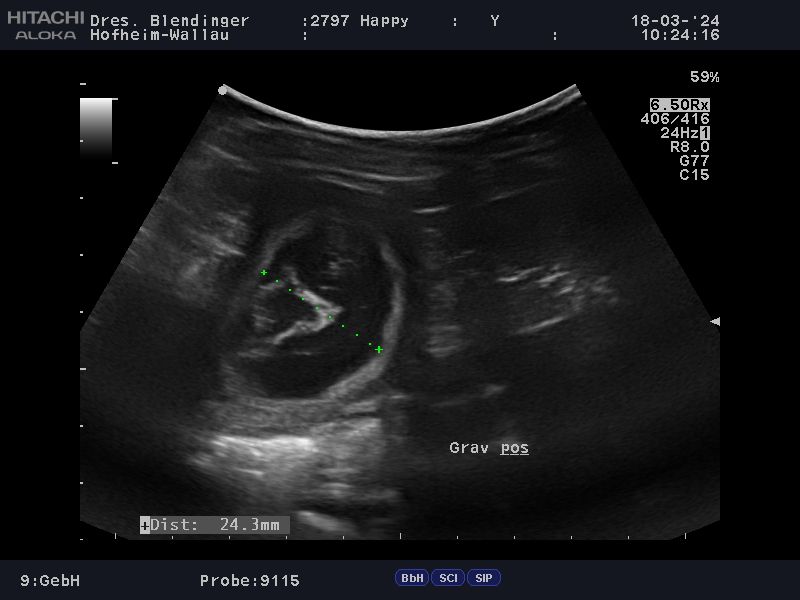

Das, was wir schon vermutet hattten, wurde uns heute, durch unseren Tierarzt bestätigt: Happy"ist trächtig . Wir werden um den 20.04.2024 Welpen in noir bekommen. Es wird für Happy ihr  letzter Wurf sein. Sie hat immer große Würfe gehabt und hat diese problemlos großgezogen. Wir hoffen und wünschen uns das es bei ihrem letzten Wurf auch so schnell, geht wie bei ihren beiden ersten Würfen. Namen mit L werden diesmal gesucht, drei Namen stehen schon fest La Luna , Le Soleil un L´Jiott. Nun haben wir noch ein paar Wochen vor uns und die Vorbereitungen können  beginnen